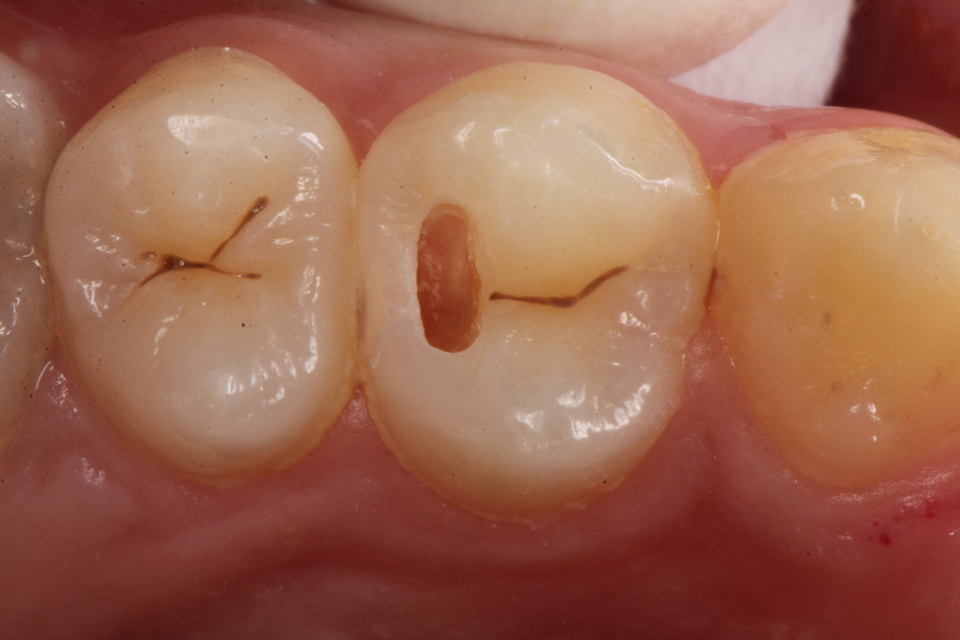

下顎7番の頬側歯茎部カリエスの原因 2025.06.04